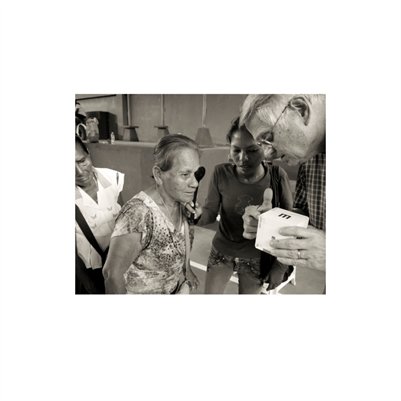

Darkness into the Light. In 2012, The Amazon Project gave eye care to nearly 6000 patients within a 200 kilometer radius of their base in Leticia, Colombia.